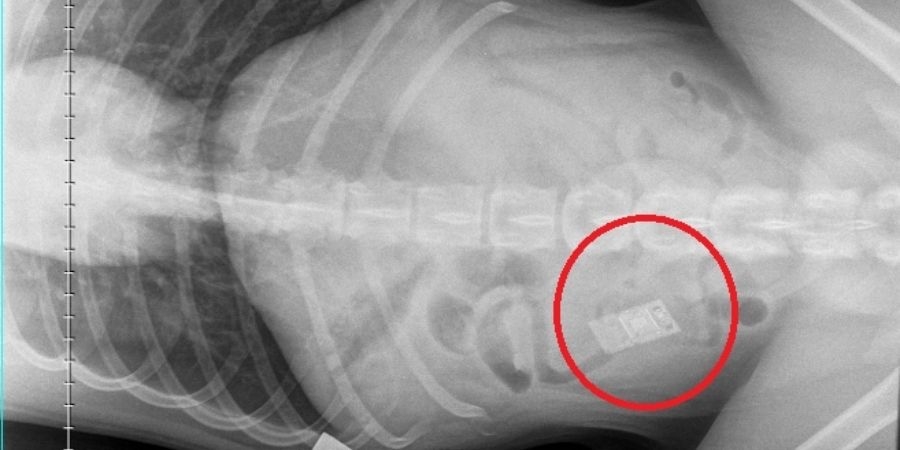

X-ray showing Nintendo DS inside stomach

5. Nintendo DS game

It was almost game over for Rocco when PDSA Vets discovered the curious canine had swallowed a Nintendo DS game. He started vomiting and refused to eat, so his owners took him to PDSA Glasgow Shamrock Street Pet Hospital for an emergency appointment. Vets found a rectangular-shaped object in his gut on x-rays and performed emergency surgery to remove it immediately. They were stunned to retrieve a video game cartridge from his small intestine, but thankfully, Rocco survived and was able to go home to rest and recover the following day.